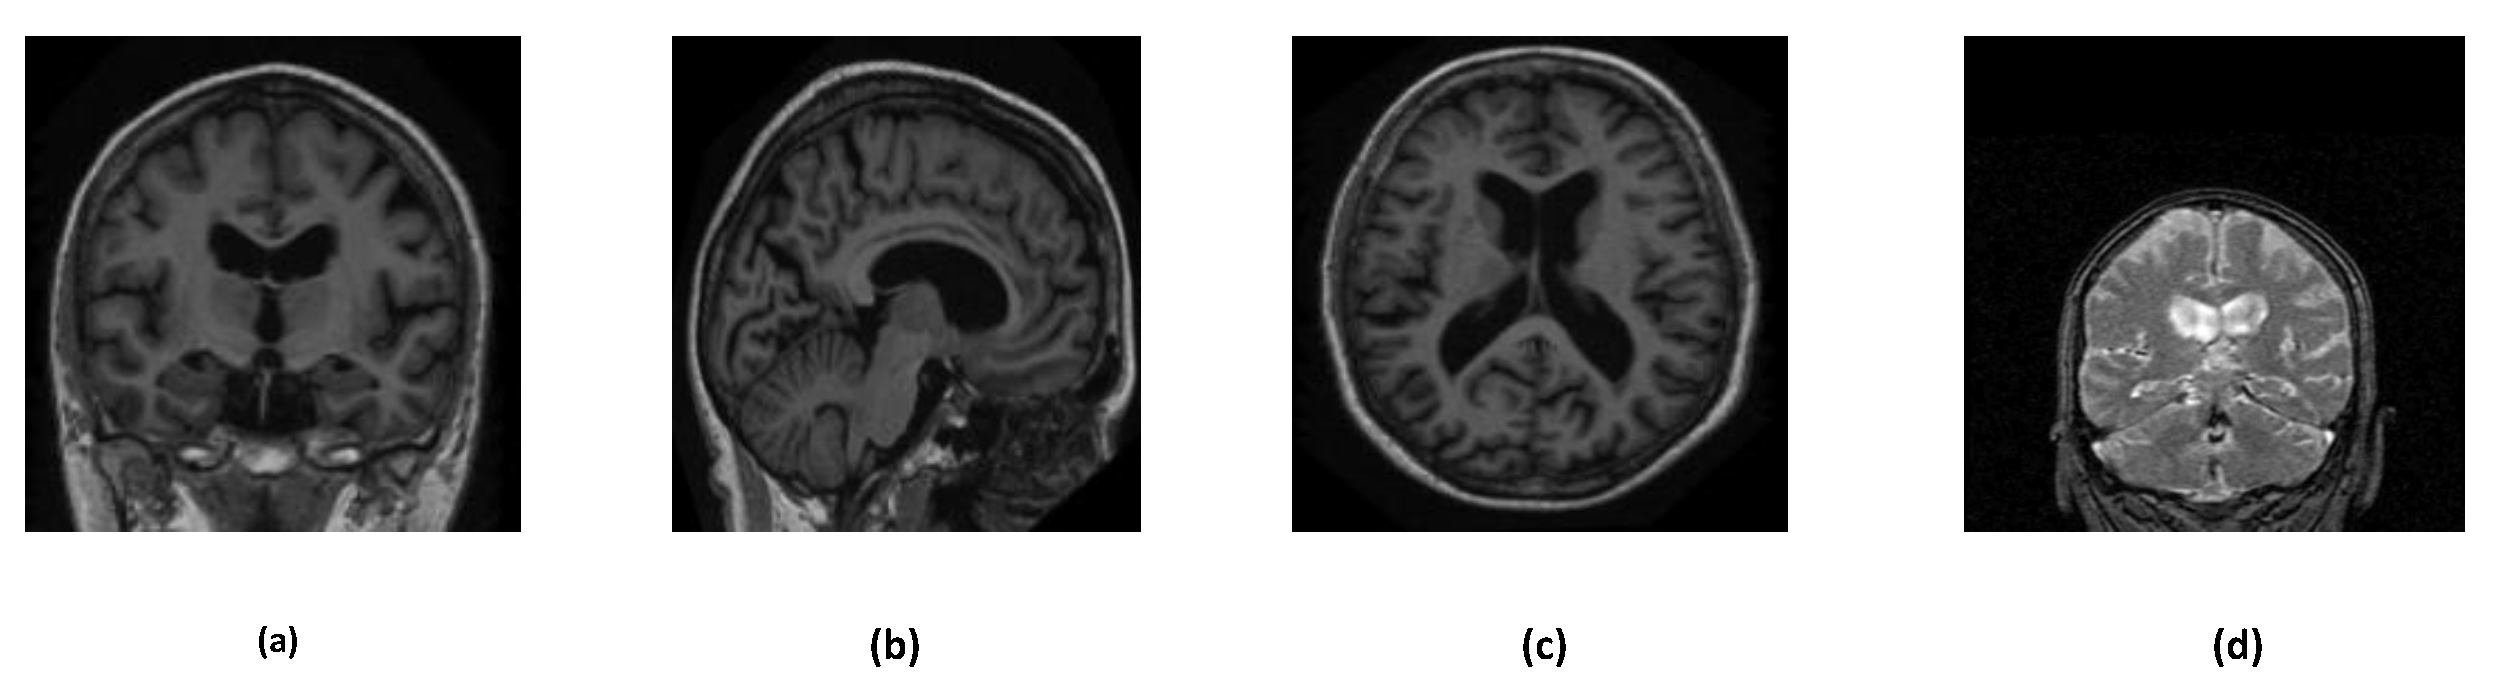

Alzheimer’s disease can be detected in many ways, such as, brain MRI, PET scan images, neurological evaluations, and so on. In this study, we have used two different brain MRI images dataset: ADNI and OASIS. Further, these datasets are divided into many subsets including augmented sets, merged sets etc. Figure 3 describes the overall structure of the datasets. Various orientations of MRI images are depicted in Figure 2.

Figure 2. Different orientations of the OASIS and ADNI dataset MRI images. (a) Coronal Plane (OASIS dataset) (b) Sagittal Plane (OASIS dataset) (c) Transverse Plane (OASIS dataset) (d) Coronal Plane (ADNI dataset)